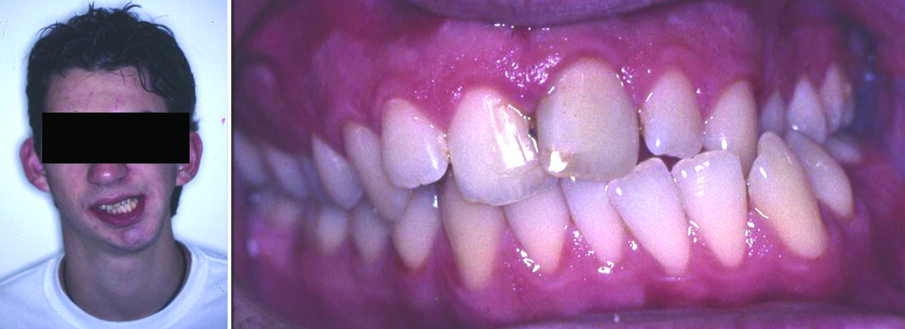

Hemimandibular hyperplasia is an uncommon maxillofacial deformity characterized by increased ramus height, rotated facial appearance, and kinking at the mandibular symphysis. Usually it is associated with prominence of the lower border of the mandible, maxillary and mandibular alveolar bone overgrowth, compensatory canting of occlusal plane, and serious functional malocclusion (4) (Figure 3). Heminandibular hyperplasia presents diffuse enlargement of the condyle, the condylar neck, the ramus, and the body of the mandible, it usually begins before puberty, is clearly due to hyperactivity in the condyle, whose cartilage actively proliferates.

Figure 3. Facial photograph of a 16-year-old girl with heminandibular hyperplasia (right side). The discrepancies include asymmetries in the mandibular body, ramus, and condyle (a). Malocclusion is characterized by left anterior crossbite and lower dental midline deviation to the non-affected side (b).